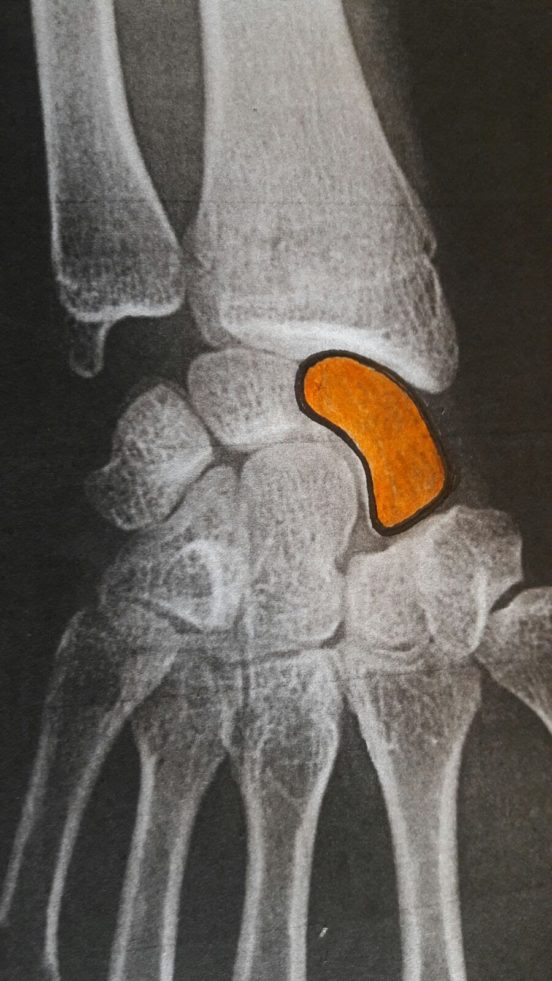

El escafoides, en color.